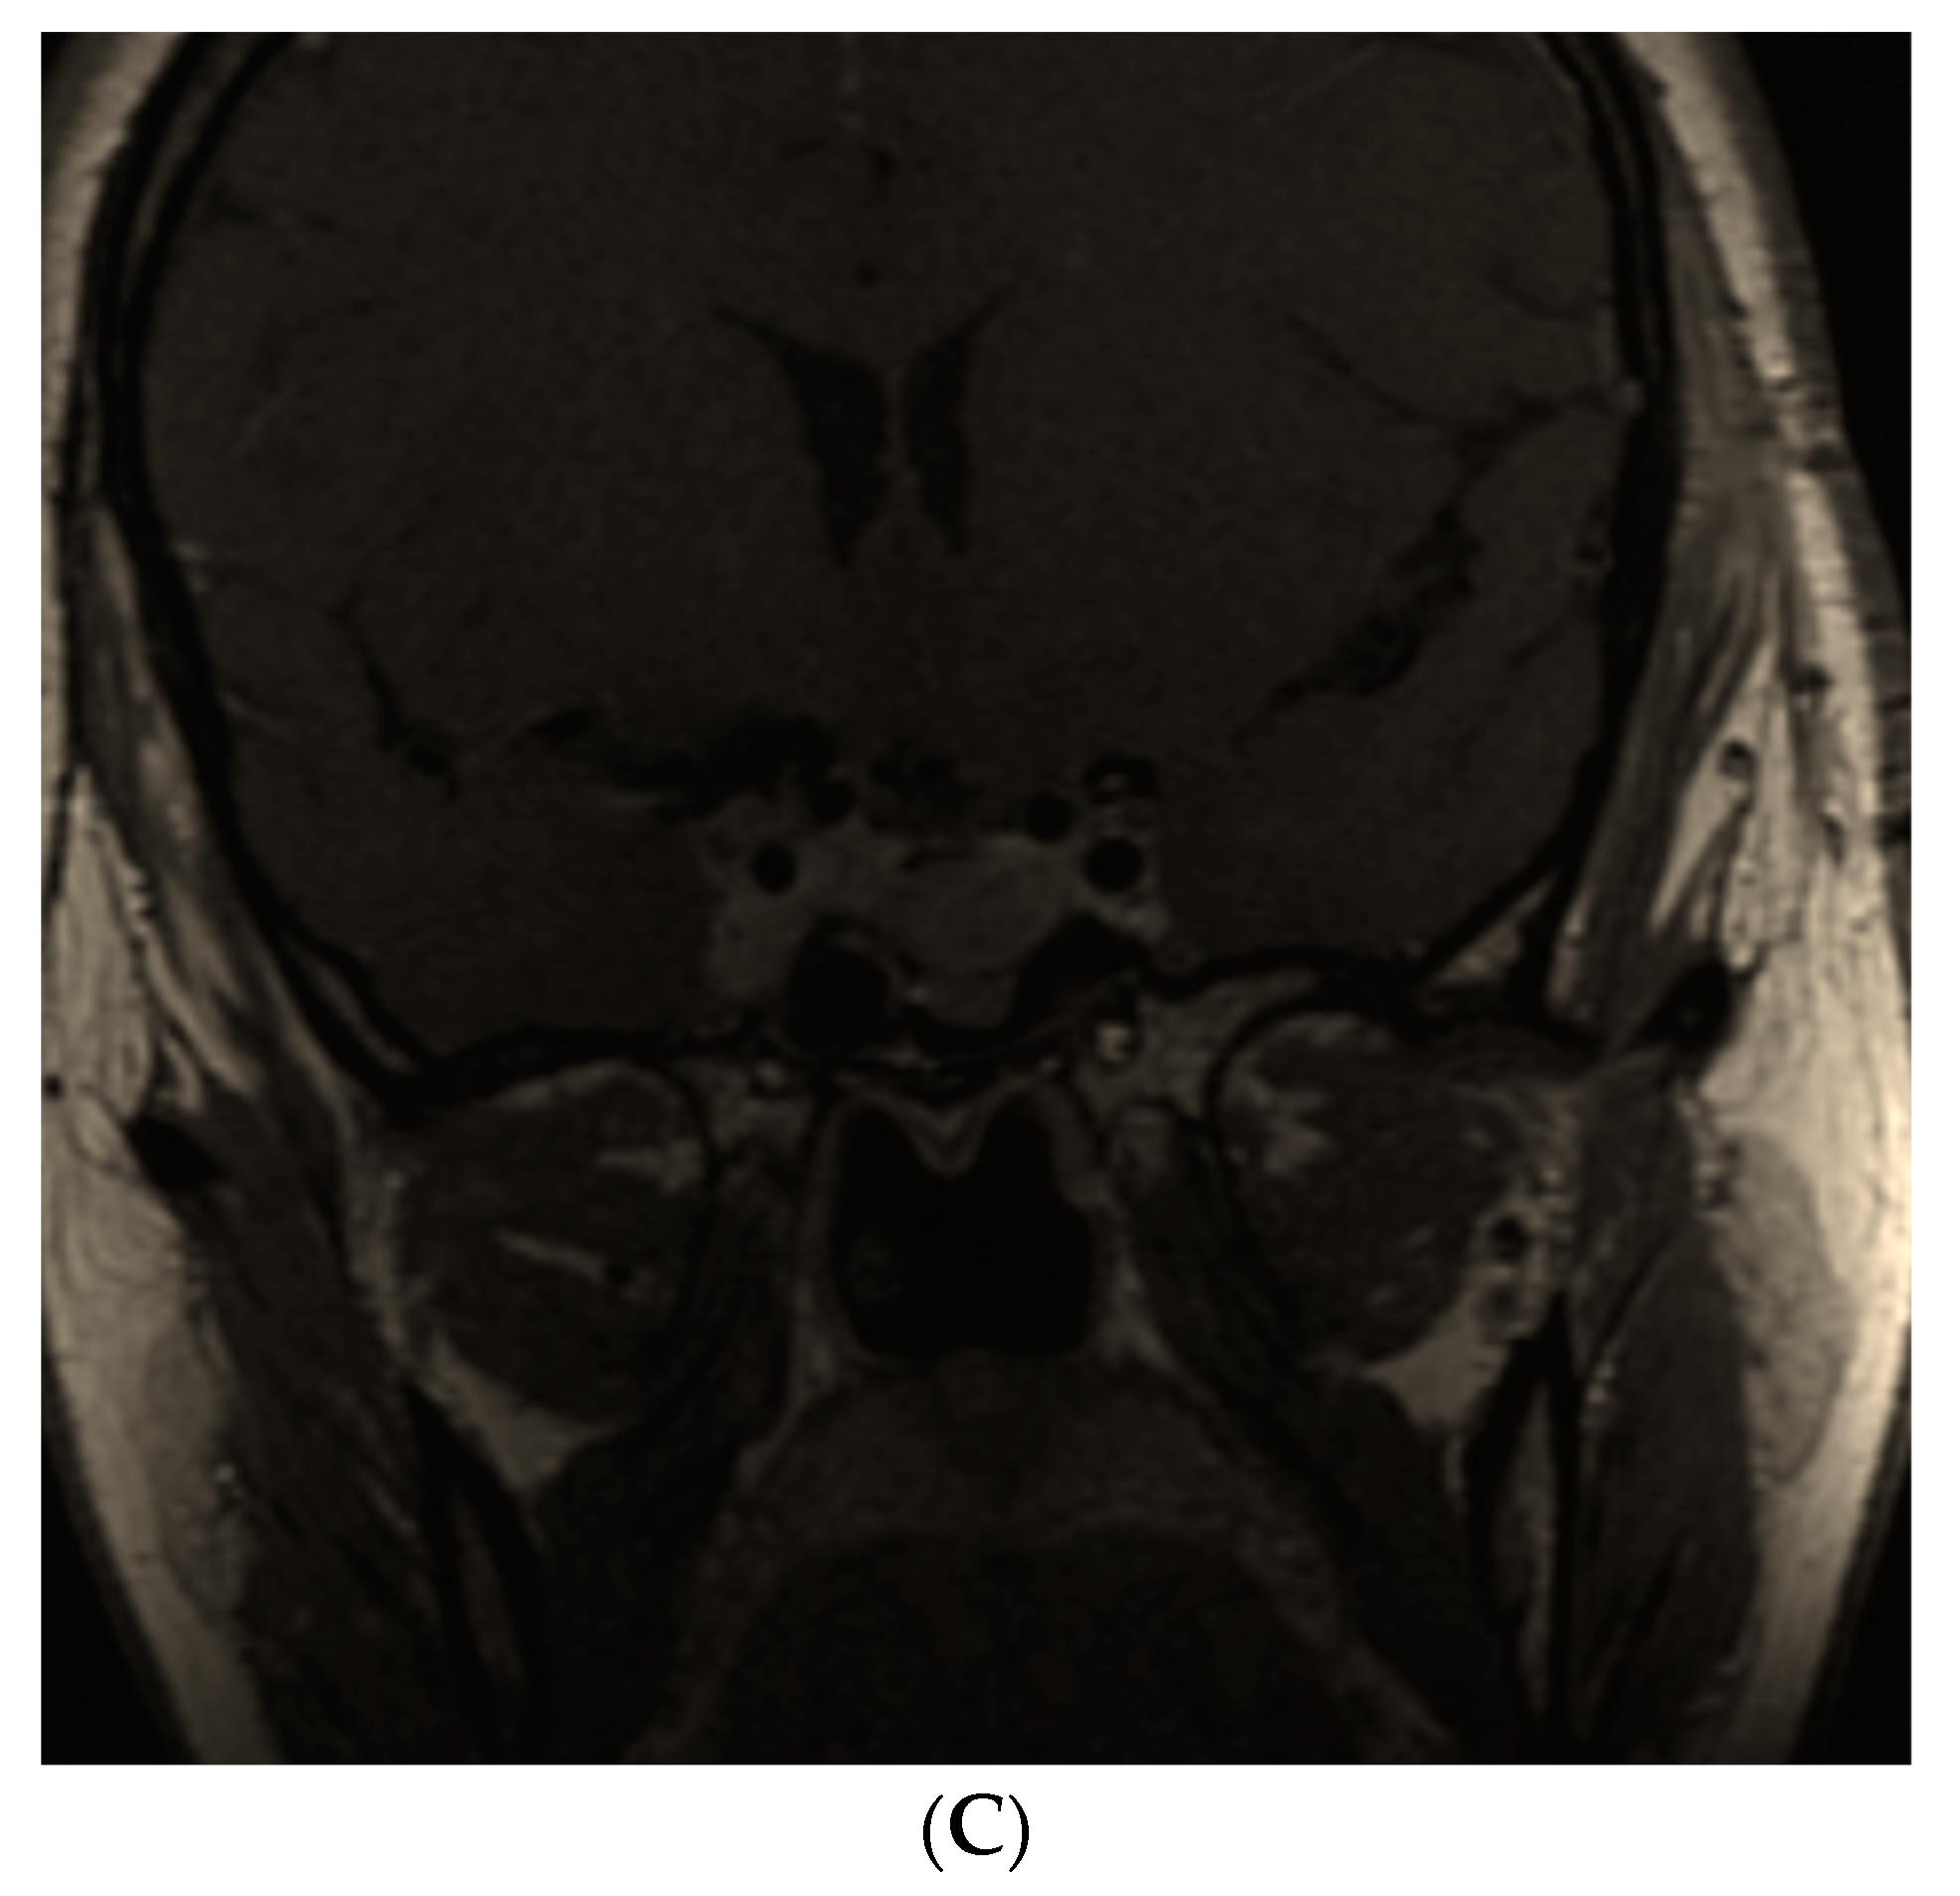

- Hannon, A.M.; Frizelle, I.; Kaar, G.; Hunter, S.J.; Sherlock, M.; Thompson, C.J.; O’Halloran, D.J.; Irish Pituitary Database Group. Octreotide use for rescue of vision in a pregnant patient with acromegaly. Endocrinol. Diabetes Metab. Case Rep. 2019, 2019, 19-0019. [Google Scholar] [CrossRef] [PubMed]

- Dicuonzo, F.; Purciariello, S.; De Marco, A.; Guastamacchia, E.; Triggiani, V. Inoperable Giant Growth Hormone-secreting Pituitary Adenoma: Radiological Aspects, Clinical Management and Pregnancy Outcome. Endocr. Metab. Immune Disord. Drug Targets 2019, 19, 214–220. [Google Scholar] [CrossRef]